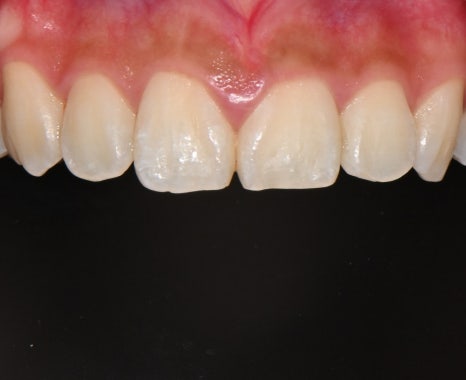

📸 Before

– Dark tooth tone

– Slightly asymmetrical tooth line

📸 After

– Brighter, smoother tooth tone

– Balanced front tooth line

– Natural shaping that harmonizes with the smile line